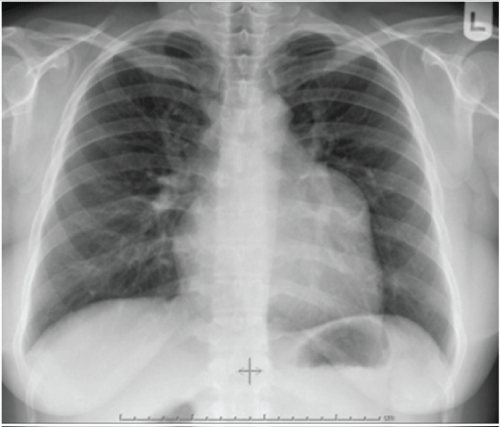

Asymptomatic healthy, 32-year-old woman was found to have enlarged left upper cardiac border on chest radiograph (CXR), undertaken as a routine health check-up (Figure 1). This was compared to a previous CXR taken 5 years earlier, which only showed a small bulging of the left upper cardiac border. Electrocardiogram showed normal sinus rhythm. A transthoracic two-dimensional echocardiogram showed left atrial appendage (LAA) aneurysm (Figure 2).

Figure 5: Post-operative chest radiograph showing normal left upper cardiac border